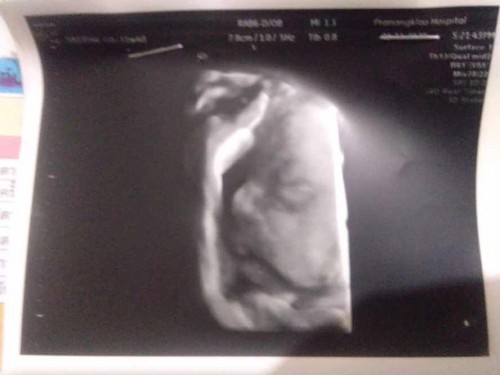

อวดเพศ ทีมมกราคม❤️

สวัสดีค่ะพี่ๆป้าๆน้าๆทุกคนมาลูกสาวมาอวดนิดนึง ดั้งมาเต็มเลย☺️ ขี้อายกว่าจะถ่ายได้ลุ้นอยู่นานมาก😂 31+4 เเล้วจ้าคุ้มกับการรอคอยมากค่ะ☺️